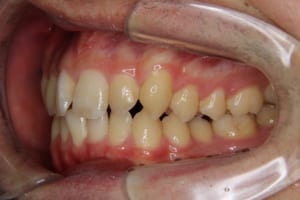

叢生、上下の歯列弓の狭窄の症例

Before

治療前

| 主訴 | 前歯の歯並びが乱れている 歯が内側に倒れている |